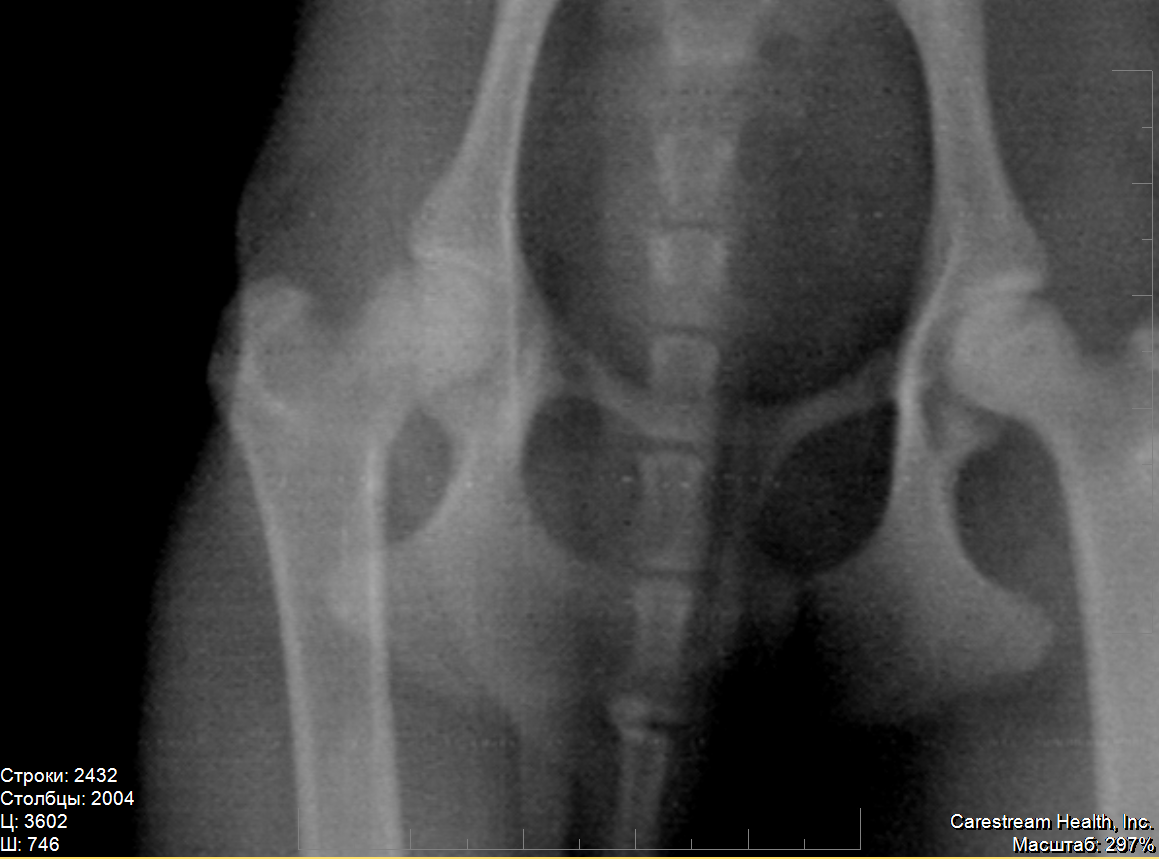

Вот теперь более-менее понятна картина. По перечисленным симптомам очень похоже на болезнь Пертеса, или остеохондропатию головки бедренной кости. На снимке явно заметна деформация головки правого сустава, левый в порядке: круглый, ровный, гладкий. Трещины на правом не видно, поэтому я бы не стала исключать другой диагноз. Врачу, конечно, виднее, но снимки можно показать и другому специалисту и выслушать его мнение. Пертес часто ошибочно связывают с травматикой, в то время как заболевание имеет наследственный характер и чаще ему подвержены мелкие породы собак. Подробнее - в интернете, а мне больше нечего добавить. Надеюсь, собачка получит своевременную помощь и лечение.

Lika-MV, к сожалению, Вы оказались абсолютно правы: это болезнь Пертеса. Причём, врач предположил это сам, после осмотра, ещё до того, как сделал снимки, несмотря на то, что заключение центровета было "трещина".

Снимков делали два, но второй снимок аж три раза: всё время Скобелева качество не удовлетворяло. Диагноз подтвердился: "асептический аваскулярный некроз головки правой бедренной кости"

на всякий случай приложу ещё два увеличения

на всех снимках слева - правая нога